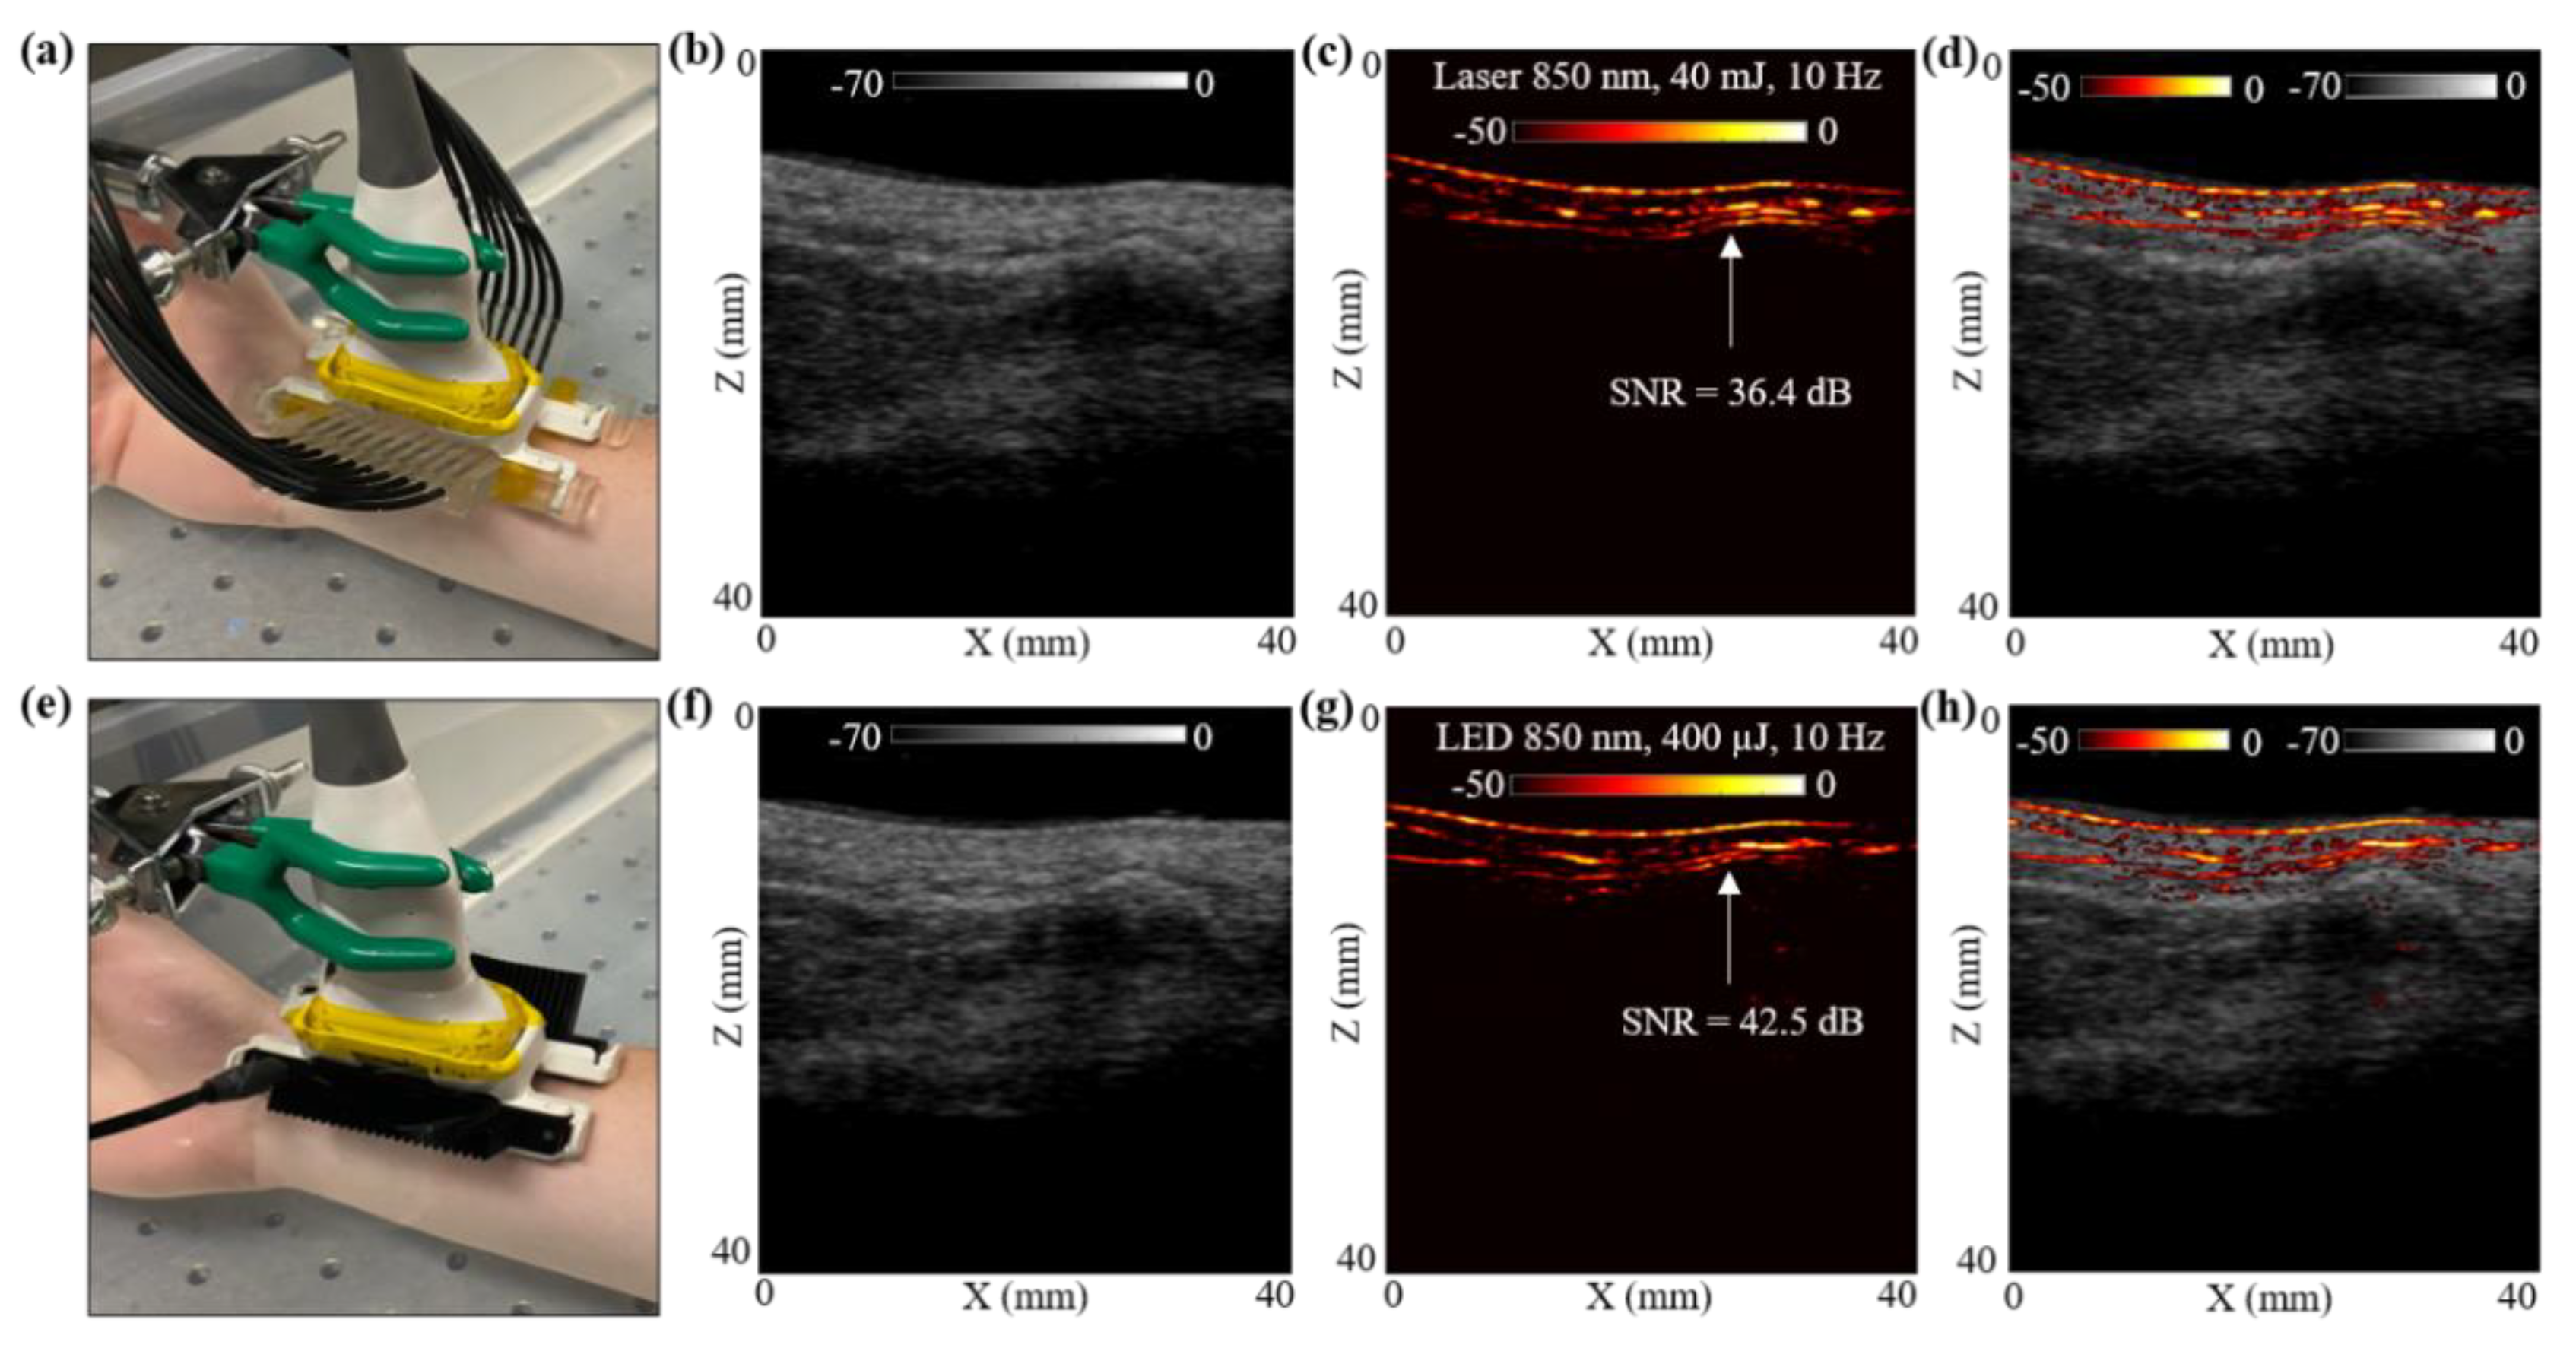

Figure 5.

In vivo comparison of LED array-based and laser-based PA vasculature imaging over the right-hand wrist of a healthy 25-year-old male human volunteer. (a) Shows the experimental setup with the right-hand wrist placed inside a big water bath for the laser-based PA imaging. (b–d) Show the obtained US, PA and coregistered US + PA images for the setup shown in (a). (e) Shows the setup with LED arrays. (f–h) Show the obtained US, PA, and coregistered US + PA images for the setup shown in (e).

The hand was first imaged with the laser-PAUS setup by attaching the laser fiber holders to the US probe, as shown in Figure 5a. The laser was operated at 850 nm wavelength, 10 Hz PRF, and delivered output optical energy of 40 mJ. This allowed ANSI safety limits of <20 mJ/cm2 optical fluence on the hand surface [59]. During the real-time data acquisition, the probe was aligned such that the major blood vessel could be seen running parallel to the skin surface in the PA images. The captured US and PA raw data using the AcousticX software were later extracted in the MATLAB software and were reconstructed to generate the beamformed images. The beamformed, log-compressed B-mode US, PA and the coregistered US + PA images are shown in Figure 5b–d. The US image showed the anatomical features along the depth of human wrist, whereas the PA image highlighted the major blood vasculature. There was fairly strong correspondence between the locations of the blood vessel in the PA image and the appearance of anechoic regions in the US image. Based on the anatomy of the vasculature in human wrist, the PA signals ~5 mm below the skin surface may have corresponded to the radial artery that travels across the front of the elbow, deep under the muscle until it comes to the wrist where it comes close to the skin surface. This is also marked with a white arrow in the PA image in Figure 5c.

To compare these laser-illumination results of the human wrist with the LED arrays, the laser-fiber attachments were gently removed without disturbing the location of the US probe. The two 850 nm LED arrays were then attached to the US probe, as shown in Figure 5e. With a PRF of 4 KHz and frame averaging of 384, leading to a frame rate of 10 Hz, the US and PA frames were captured using the LED array setup. The US and PA raw data were then reconstructed in MATLAB. Figure 5f–h show the beamformed log-compressed B-mode US, PA and coregistered US + PA images for the human wrist. As in the case of laser illumination, the LED array-based PA images also imaged the same vasculature below the skin surface. The radial artery present ~5 mm below the skin was clearly visible with the LED array-based acquisition as well.

To further compare the two setups quantitatively, an SNR comparison study was performed for the radial artery, as marked with white arrows in Figure 5c,g. To calculate the SNR, the peak PA signal at the artery and the mean noise adjacent to the artery region was calculated over the linear beamformed PA images resulting from the laser-illumination and the LED array-based acquisitions. Table 3 presents the values of peak PA signal, mean noise and the SNR. The SNR values are also marked in the Figure 5c,g. Both the peak signal and mean noise with the laser are up to three log orders of magnitude higher compared to the LEDs. However, the SNR value for the laser-illumination-based PA image was about 6 dB lower than the SNR with the LED array acquisition. This follows the trend observed for the controlled tissue phantom studies discussed in Section 3.1, where the shallow targets (<30 mm) inside an intralipid medium were detected with higher SNRs using LED arrays compared to the laser illumination, maintaining the same frame rate.

In the final study, in Section 3.4 we presented an in vivo LED-PAUS and laser-PAUS imaging of the wrist of a healthy human volunteer. Figure 5 presents the qualitative and quantitative comparison results for a radial artery seen ~5 mm below the wrist skin surface. Analysis of the peak PA signal, mean noise and SNR for this radial artery is presented in Table 3. As observed with the studies presented in previous sections, for a shallow depth target, the LED-PAUS showed better SNR than the laser-PAUS at the same 10 Hz frame rates. The ~5 mm deep radial artery was imaged with a 36.37 dB SNR with the laser compared to a 42.49 dB SNR with LED arrays. This study substantiates that the LED-PAUS imaging is an attractive choice for several preclinical and clinical applications.